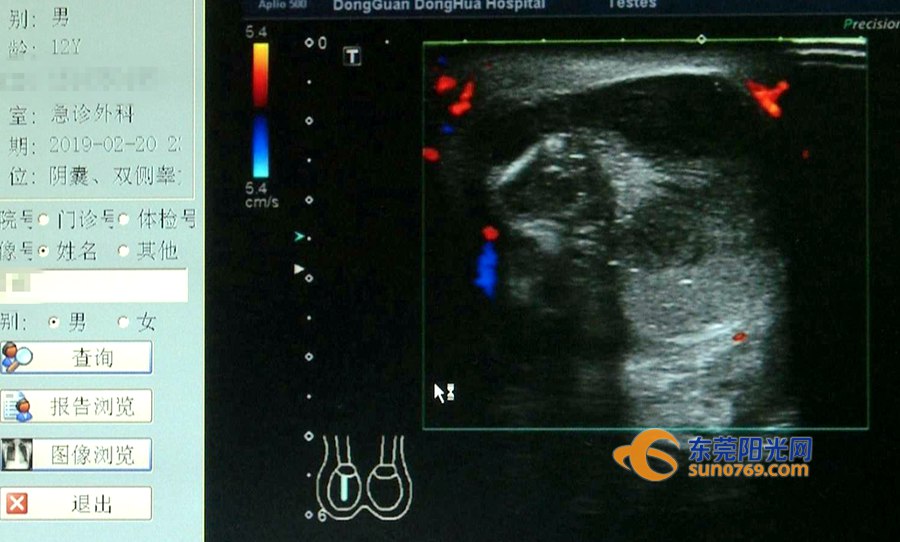

2月21日凌晨,一位焦急的家长抱着孩子冲入东华医院泌尿科,称孩子阴囊肿得像皮球一样。医生检查后发现,该男童右侧*丸睾**红肿胀大,直径十公分左右,右侧*丸睾**没有了血流信号,意味着很可能已经因为血管堵塞而坏死。

随后,医生对患者安排了急诊手术,发现右侧*丸睾**已经顺时针方向扭转了360度,手动复位之后用温水、温毛巾热敷,依然没有血流信号。由于右侧*丸睾**呈黑色已经坏死,只能被切除。检查还发现,其左侧*丸睾**也存在解剖缺陷和发育异常,所以医生用缝线把左侧的*丸睾**缝到阴囊壁上,防止以后再发生扭转导致坏死的事情。